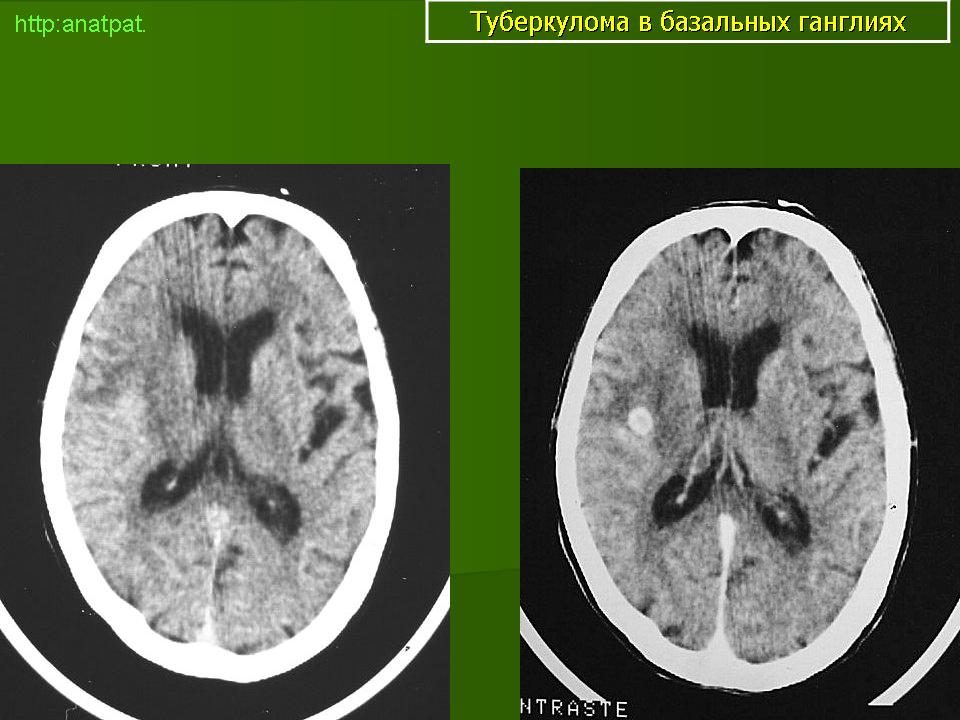

Туберкуломы.